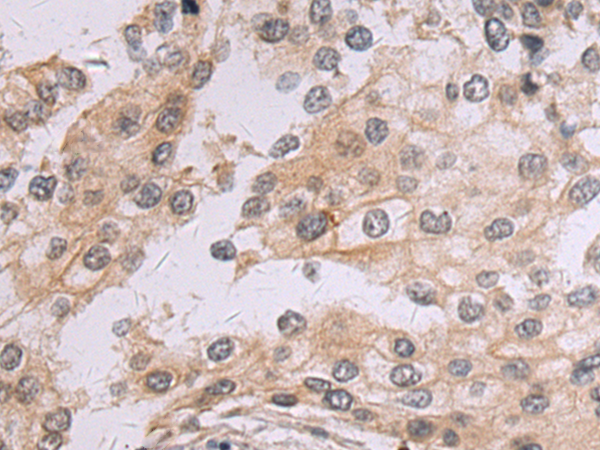

IHC positive control: |

Human colorectal cancer |

IHC Recommend dilution: |

50-100 |